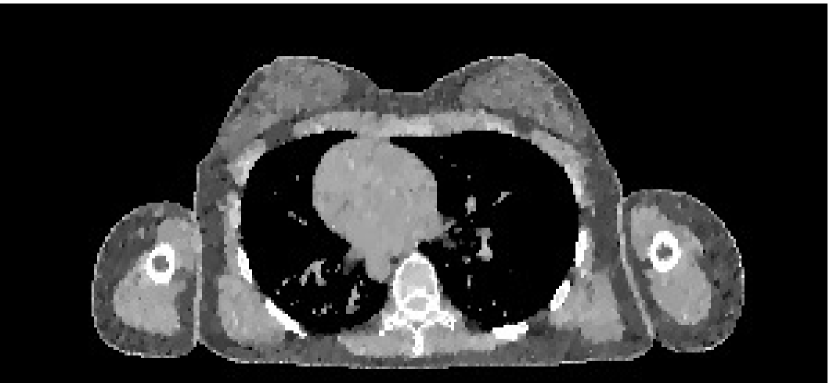

The data we used for our numerical reconstruction test were derived from the Adult Reference Computational Phantom (ICRP Publication 110,, 2009), which is a segmented image of defined density and chemical composition to represent real tissues. To investigate the ability to image metal implants, we inserted a pair of prosthetic hip joints (marked in green) with a solid titanium pin and shell. The slices through the chest and pelvis—which are the images we selected for testing—are shown in Figure 8. The resolution is 299×137299137299\times 137.

Refer to caption

(b) Pelvis test image

Figure 8: Experimental data used: (a) is the oracle chest electron density; and (b) is the oracle pelvis electron density; both have a with display window of [0.8,1.2]